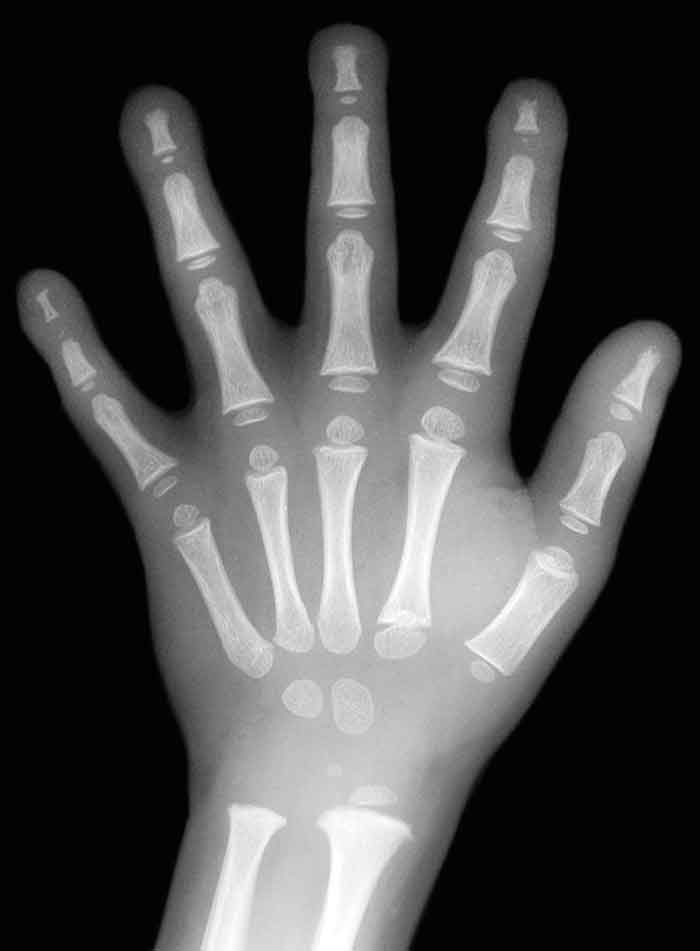

Bedömning av tand- och skelettmognad via röntgenundersökning utgör en kompletterande del av undersökningarna för medicinsk åldersbedömning.

Röntgenundersökning av handleden är en metod som utvecklades för att prognostisera slutlängd. Tillväxtzonens storlek bedöms och jämförs med en tabell som baseras på undersökningar av barn i olika åldrar, vanligen en tabell som skapades på basis av vita amerikanska barn från medelklassen födda på 1930-talet [1].

I en nyligen publicerad studie undersöktes skelettmognad med handledsröntgen hos barn i Sydafrika [3]. Jämfört med den vanligaste referenstabellen konstaterades en genomsnittligt påtagligt tidigare slutning av tillväxtzonerna – mellan 1,5 och 2 år hos såväl de vita (16,5 år) som de svarta (17,0 år) pojkarna och flickorna (15,0 år) – något som starkt ifrågasätter validiteten av jämförelsematerialen för åldersbedömning i dag.

De 95-procentiga konfidensintervallen för handledsröntgen har uppskattats till 2–3 år åt vardera hållet vid denna ålder i slumpmässiga urval, och mognaden av visdomständer har uppvisat större variation än så [2, 4]. Att Migrationsverket troligen ifrågasätter åldern oftare hos ungdomar med tidig pubertet än hos dem som varit sena i sin pubertetsstart förstärker ytterligare osäkerheten i bedömningen av handledsröntgen.

Sedan 2000 har Migrationsverket utfört förenklade medicinska åldersbedömningar, vilka baserats enbart på röntgenundersökningar av visdomständer och/eller handled. På grund av metodernas breda felmarginaler tog Socialstyrelsen 2008 ställning mot användning av dem för åldersbedömning i övre tonåren [5].